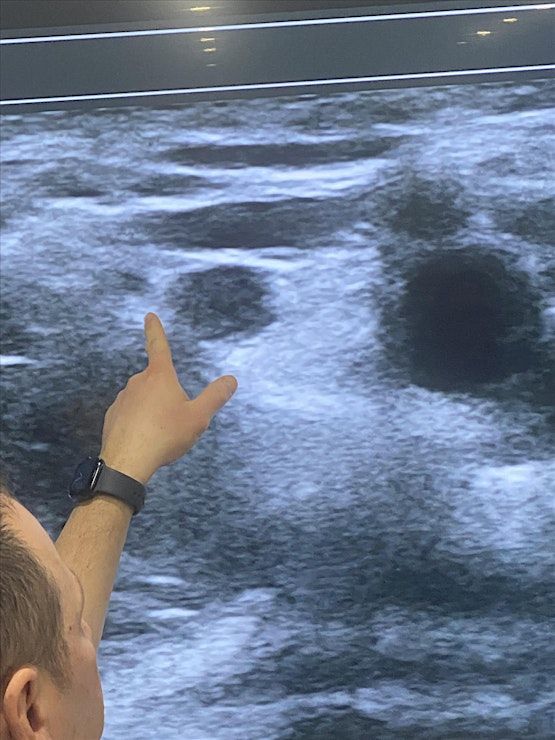

Ultrasound IV Access Workshop

This 1.5 h workshop has been developed for both novices and advanced nurses, PAs and physicians providers who would like to either learn the basic theory and practical aspects of ultrasound guided venous access.. Participants will have up to 30-60min hands on ultrasound scanning on live models and lecture to learn and identify sono‐anatomy as well as practice IV Cannulation on our phantoms. At the end of the workshop, you will be expected to have gained thorough knowledge and immense confidence in the use of ultrasound guided IV placement.

• Identify normal sono‐anatomy of the venous system

• Describe nerves and learn how to avoid them prior to IV insertion

• Demonstrate needle insertion techniques for ultrasound guided placement both in‐plane and out‐of‐plane

Live Scanning and Practice

Info: Scan the venous system and practice IV insertion on our ultrasound phantoms/